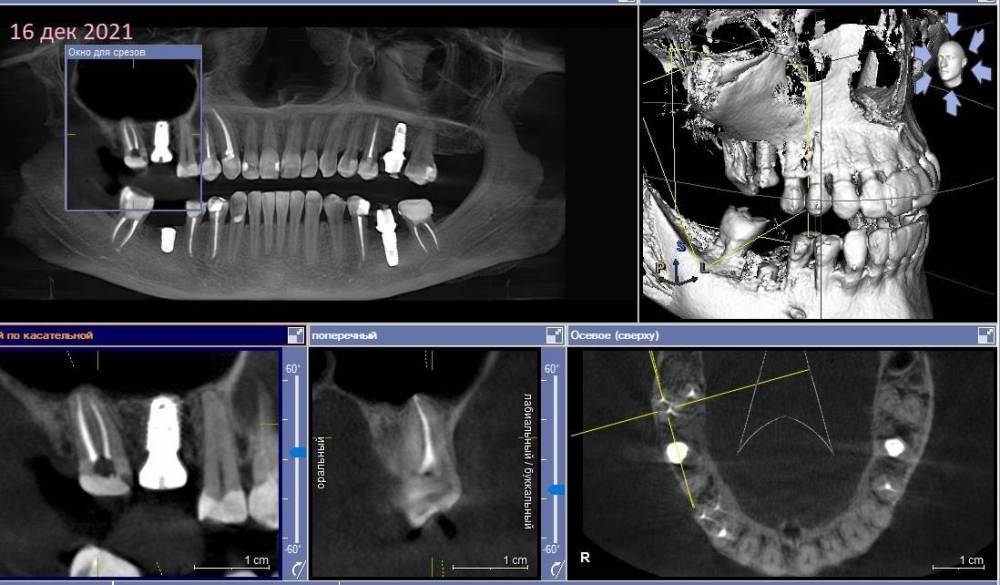

Зуб 17.

Сентябрь 2021 – удалили 16й с одномоментной имплантацией и подсыпкой кости, сразу поставили формирователь.

Недавно с ужасом обнаружила, что 17 сместился в сторону импланта 16, уткнувшись в формирователь(

3.  Почему так быстро сместился 17 в сторону 16? И помешает ли это при установке коронок на 16, 17?

КТ наскринила парочку. Если нужно будет более подробно – выложу еще.